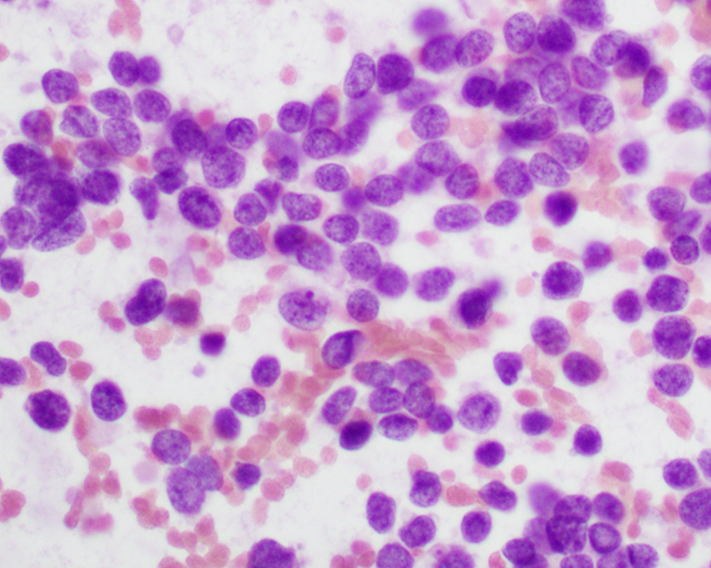

Cytology description

- Uniform small round cells (Diagn Cytopathol 2020;48:1098, Thorac Cancer 2016;7:602)

- Fine chromatin

- Occasional nucleoli

- Scant to indistinct cytoplasm

- Occasional rosette-like structures

Cytology images